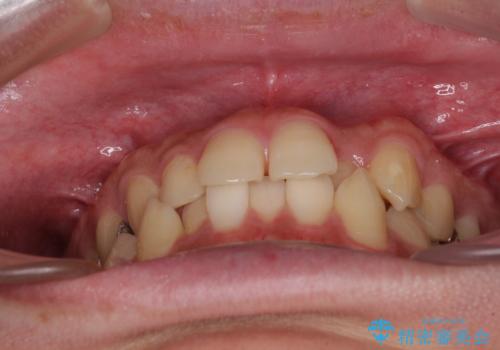

前歯のクロスバイト インビザラインによる矯正治療

- 上下のクロスバイトと前歯のデコボコを気にして来院された患者様です。

インビザラインを用い、IPR(歯と歯の間を削る)と歯列全体を拡大させることで、歯並びを整えていくこととしました。